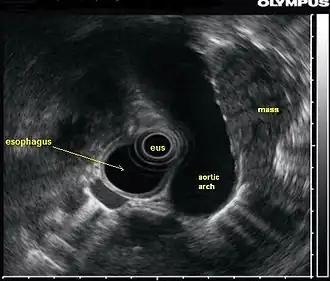

In this endoscopic ultrasound image, a mass (in this case, from lung cancer) is visualized using an ultrasound probe (EUS) inserted into the esophagus. | |

An endoscopic ultrasound probe placed in the esophagus can also be used to visualize lymph nodes in the chest surrounding the airways (bronchi), which is important for the staging of lung cancer. Ultrasound can also be performed with an endoscopic probe inside the bronchi themselves, a technique known as endobronchial ultrasound.